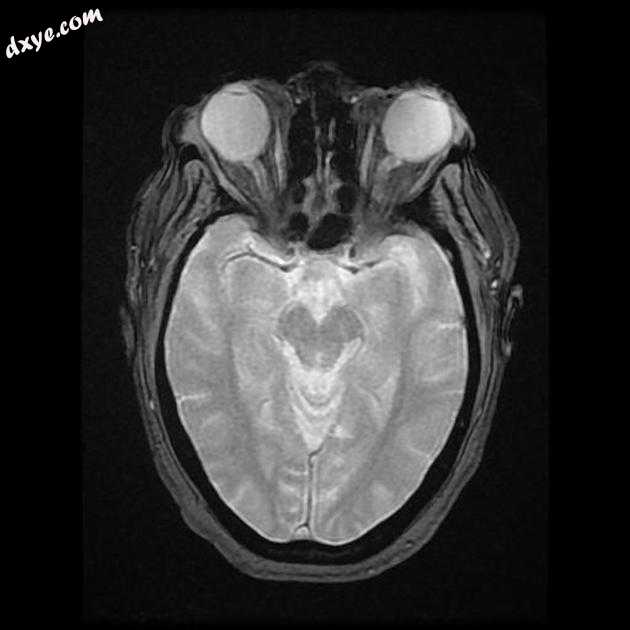

Axial FLAIR

MRI 序列显示左侧大脑中动脉 (MCA) 区域分布中的弥散受限区域,在 FLAIR 序列上不可见。在 GE 序列上没有看到出血性转化。 MRA 3D-TOF 显示左侧大脑中动脉完全闭塞。

早期超急性大脑中动脉 (MCA) 区域梗死的 MRI 特征。